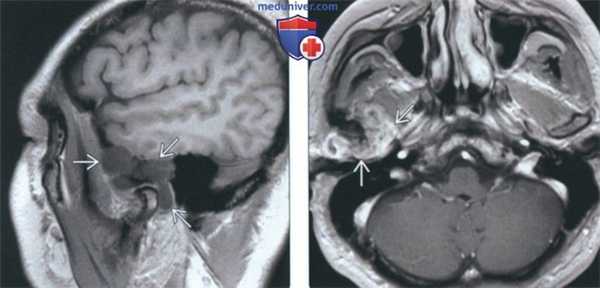

(Слева) На аксиальной КТ без КУ определяется ХС правого мыщелка, снаружи от которого видны множественные плотные включения в отсутствие явного объемного образования. Внутренний край мыщелка склерозирован. Обратите внимание, насколько правый мыщелок отличается от неизмененного левого.

(Справа) На корональной реформатированной КТ без КУ у этого же пациента в мягких тканях визуализируется кольцевидный кальцинат с гиподенсным центром. Определяется деструкция стенок суаавной ямки и большого крыла клиновидной кости. Мыщелок увеличен.